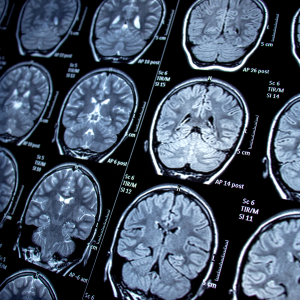

Early Diagnosis